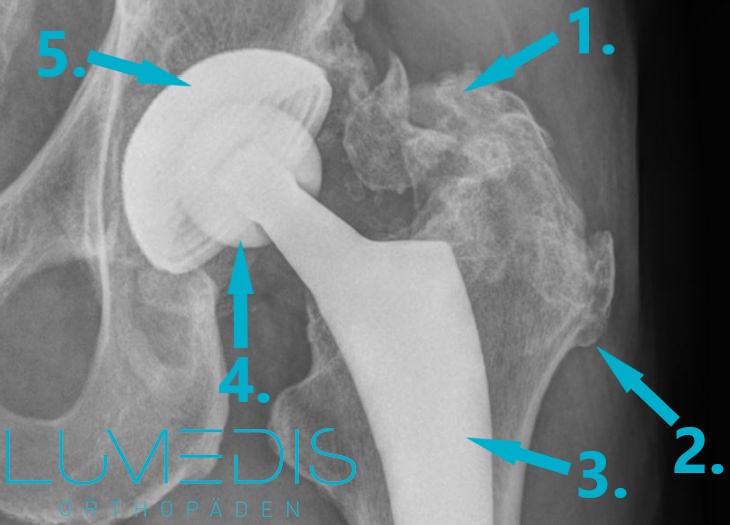

Röntgenbild einer totalen Hüftendoprothese rechts

Das Röntgenbild spielt bei der Versorgung mit einer Hüftprothese eine große Rolle.

Es liefert wichtige Informationen über den Zustand der Knochen, des Knorpels und zur Position des Hüftgelenks.

Durch moderne Röntgenverfahren wird die Strahlenbelastung so gering wie möglich gehalten.

Durch ein optimales Röntgenbild kann bereits eine digitale Planung der Hüftprothese am Computer planen.

Röntgenbild eines künstlichen Hüftgelenks links mit heterotoper Ossifikation